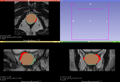

- Automatic segmentation of prostate gland on MRI data for preoperative planning and/or guided biopsy.

- Preliminary results (before project week):

Dice coefficient: median = 0.704

5° percentile = 0.485

95° percentile = 0.850

Average Hausdorff Distance (mm): median = 3.691

5° percentile = 1.790

95° percentile = 7.124

95° percentile Hausdorff Distance (mm): median = 8.903

5° percentile = 4.988

95° percentile = 17.498

- Currently results (at the end of the project week):

Dice coefficient: median = 0.750

5° percentile = 0.480

95° percentile = 0.859

Average Hausdorff Distance (mm): median = 3.047

5° percentile = 1.752

95° percentile = 6.521

95° percentile Hausdorff Distance (mm): median = 7.670

5° percentile = 4.829

95° percentile = 11.405